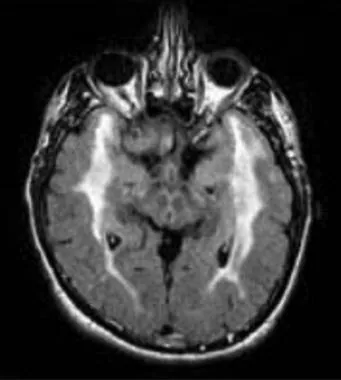

hot cross bun sign

hyperintensities of cerebellar peduncles